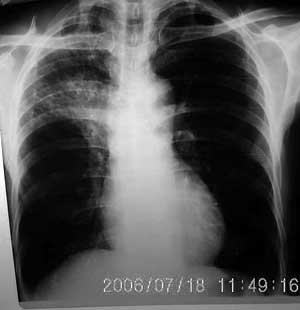

以下是引用jiangjing在2006-7-20 19:22:00的发言:[br]右侧肺门见有软组织肿块,边缘不规则,不光整,其周围肺内见炎性片状影,胸片示水平裂呈弧形上移,右上叶支气管狭窄,考虑右肺中央型肺癌伴阻塞性肺炎部分肺不张。

以下是引用1983在2006-7-20 21:53:00的发言:[br]右侧中央型肺癌伴阻塞性肺炎.

以下是引用卜一在2006-7-20 14:13:00的发言:[br]图象质量差了些,首先考虑:中心性肺癌伴阻塞性肺炎.因发生在右肺上叶尖后段,而且外带见二个空洞影,次考虑:不排除肺结核